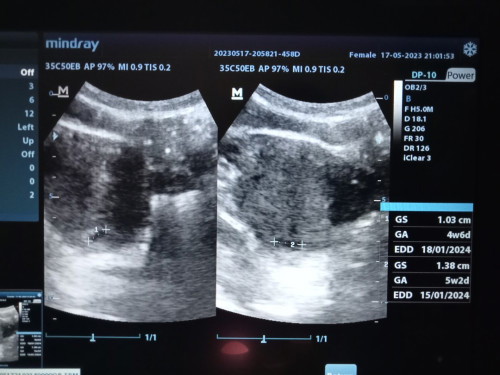

bun mau tanya ini hamil saya yg ke 2 setelah anak pertama saya keguguran dan dikuret ternyata bayinya masih ada pas 3 bln ketauannya umurnya sm kaya dikuret.. saya hamil berdasarkan HPHT 7 minggu 1 hari tapi saya usg usia janin 5 minggu 2 hari kata bidannya kehamilan saya hrs dikontrol soalnya kecil bun dilihat dari bb saya pun kecil bb 37 tb 169.. saya disuruh usg lagi 2 minggu kemudian.. saya takut banget bun trauma sm yg pertama jadi saya mutusin buat usg pas 12 week aja biar jelas udh lumayan kliatan di usg.. yg penting saya minum asm folat&vitamin dan alhamdulillah tdk ada flek sm skli cuma mabok aja.. skrg selisih sm anak pertama 1 thn 10 bln.. menurut bunda selisih 2 minggu tu normal gak yaaa ???? #seriusnanya #bantusharing #pleasehelp